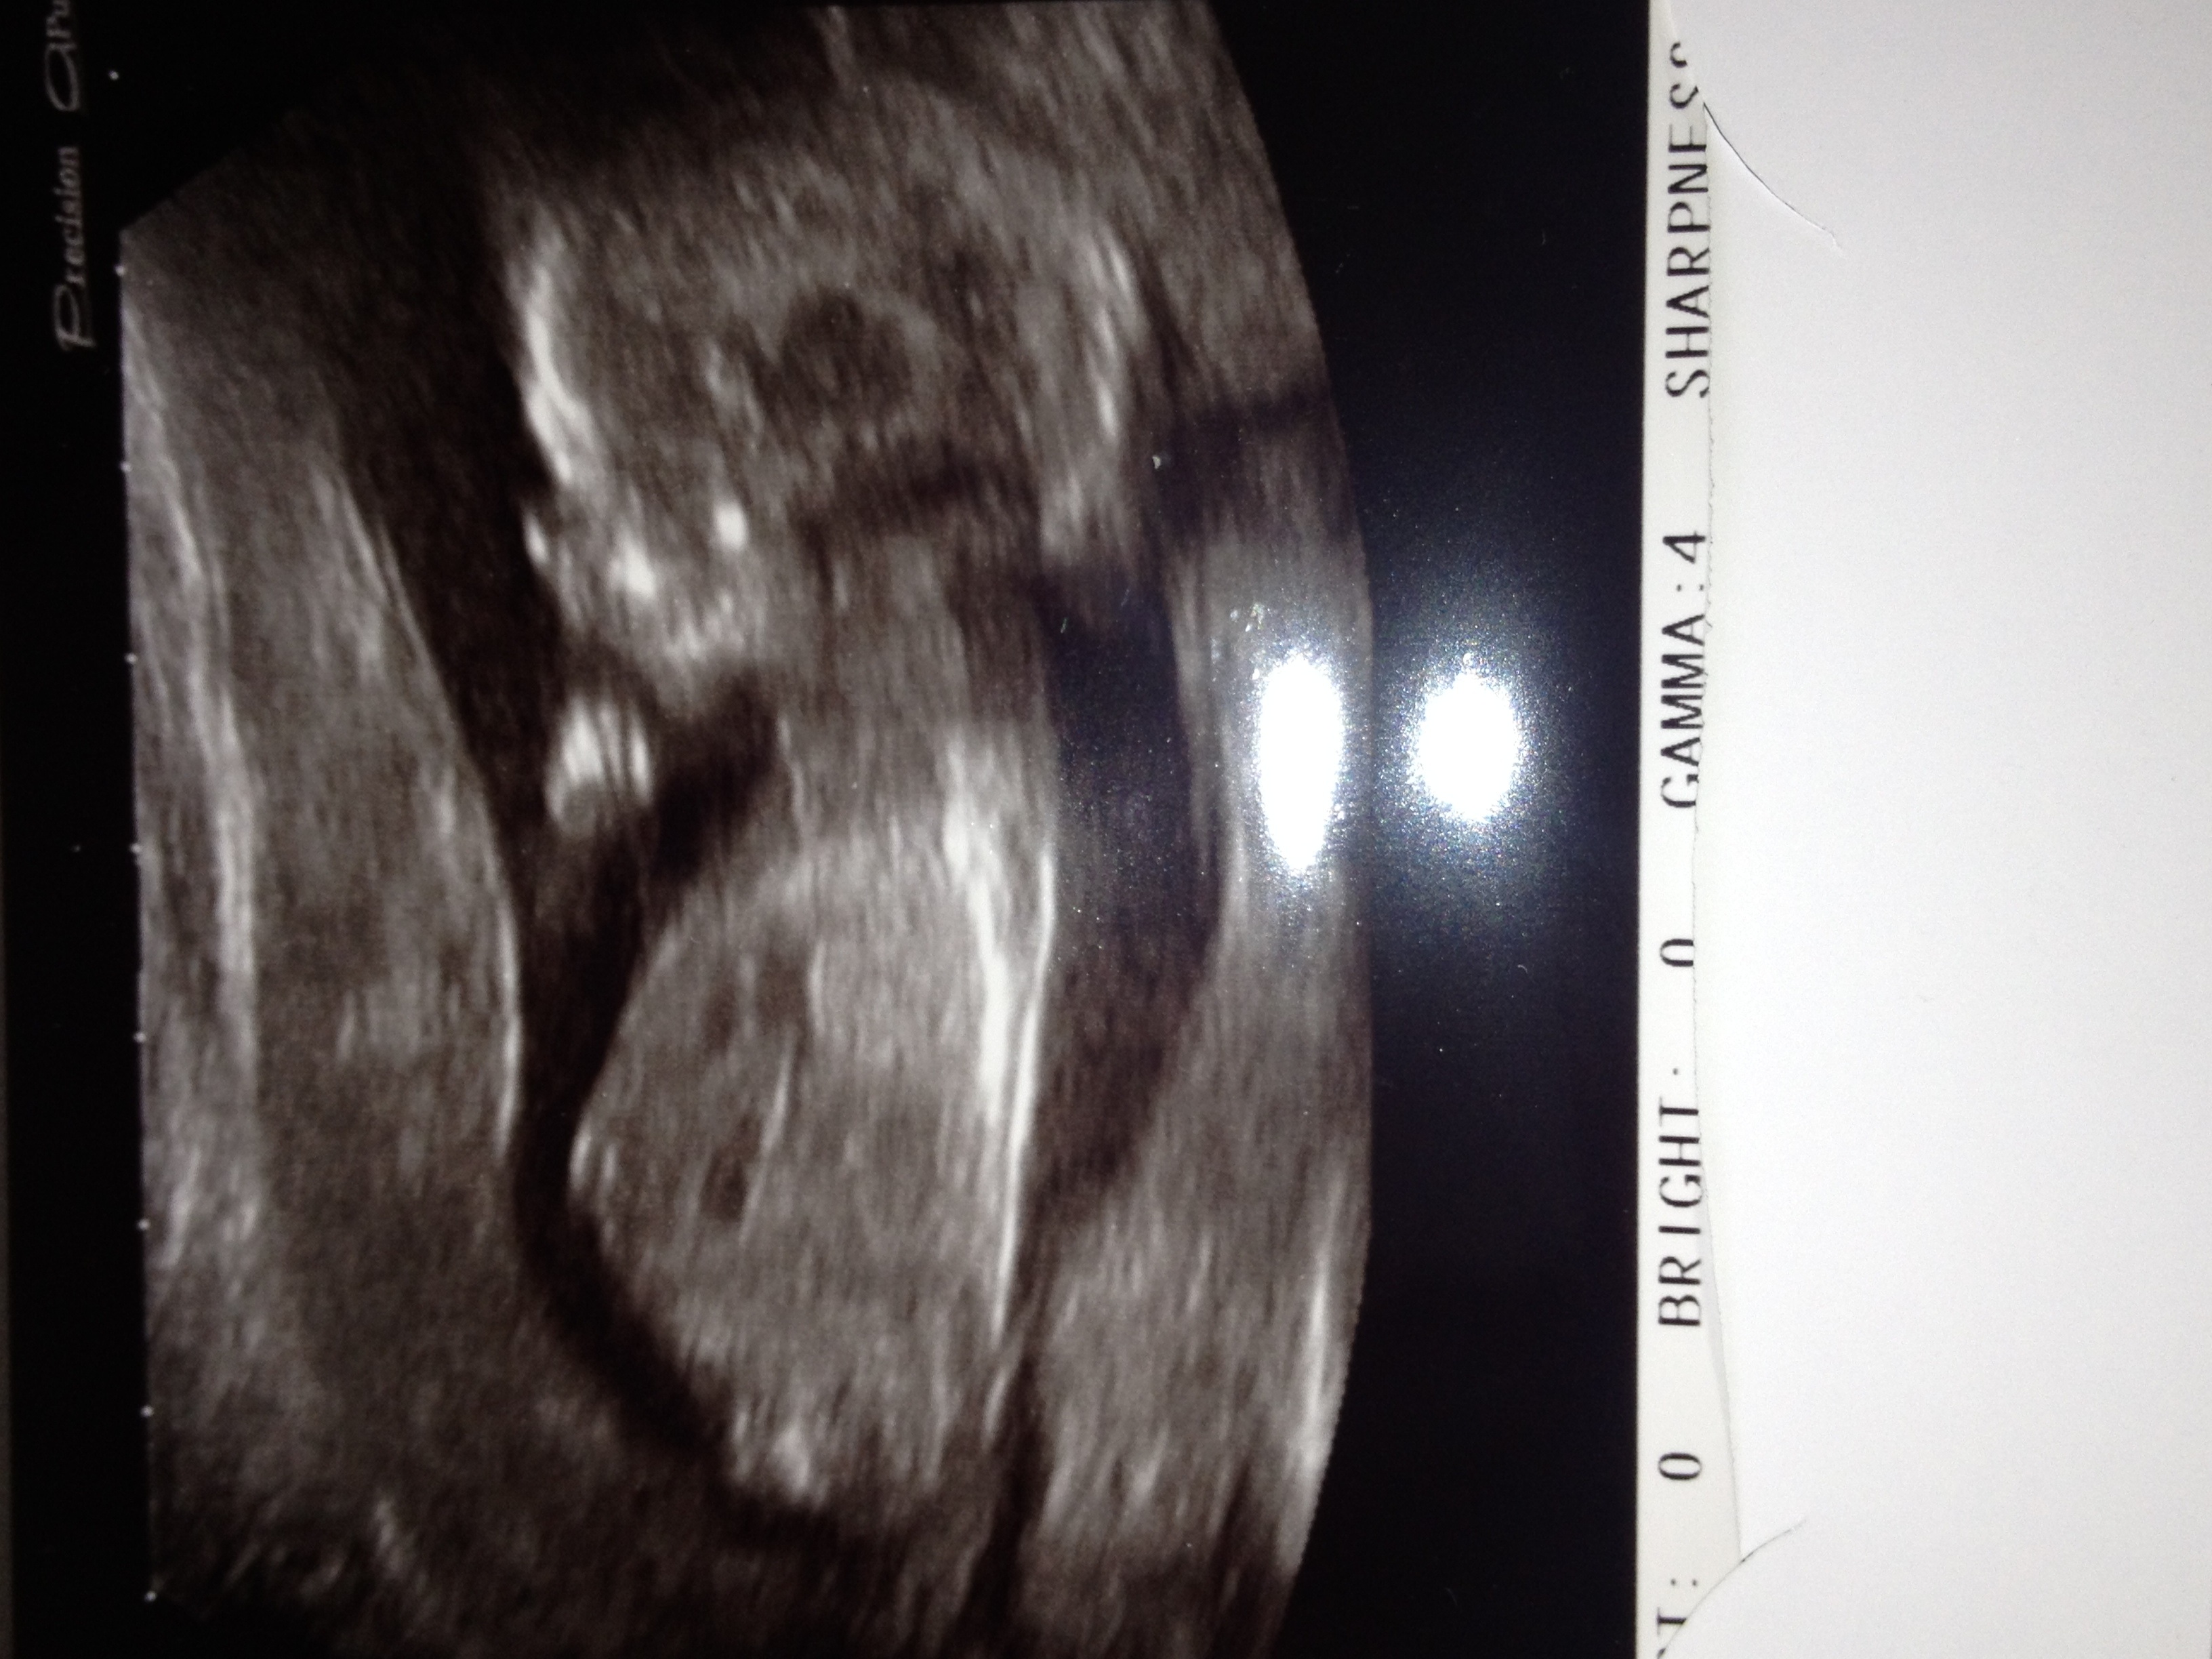

I think a girl but im no expert, what you hoping for. Is this your early scan?

Hi yes this is at 14 weeks it's just a close up shot I've had scan before where they are more far away so the baby looks smaller but this ones zoomed in :-) its not a extra large baby ha ha xxx thanks for your comment xx